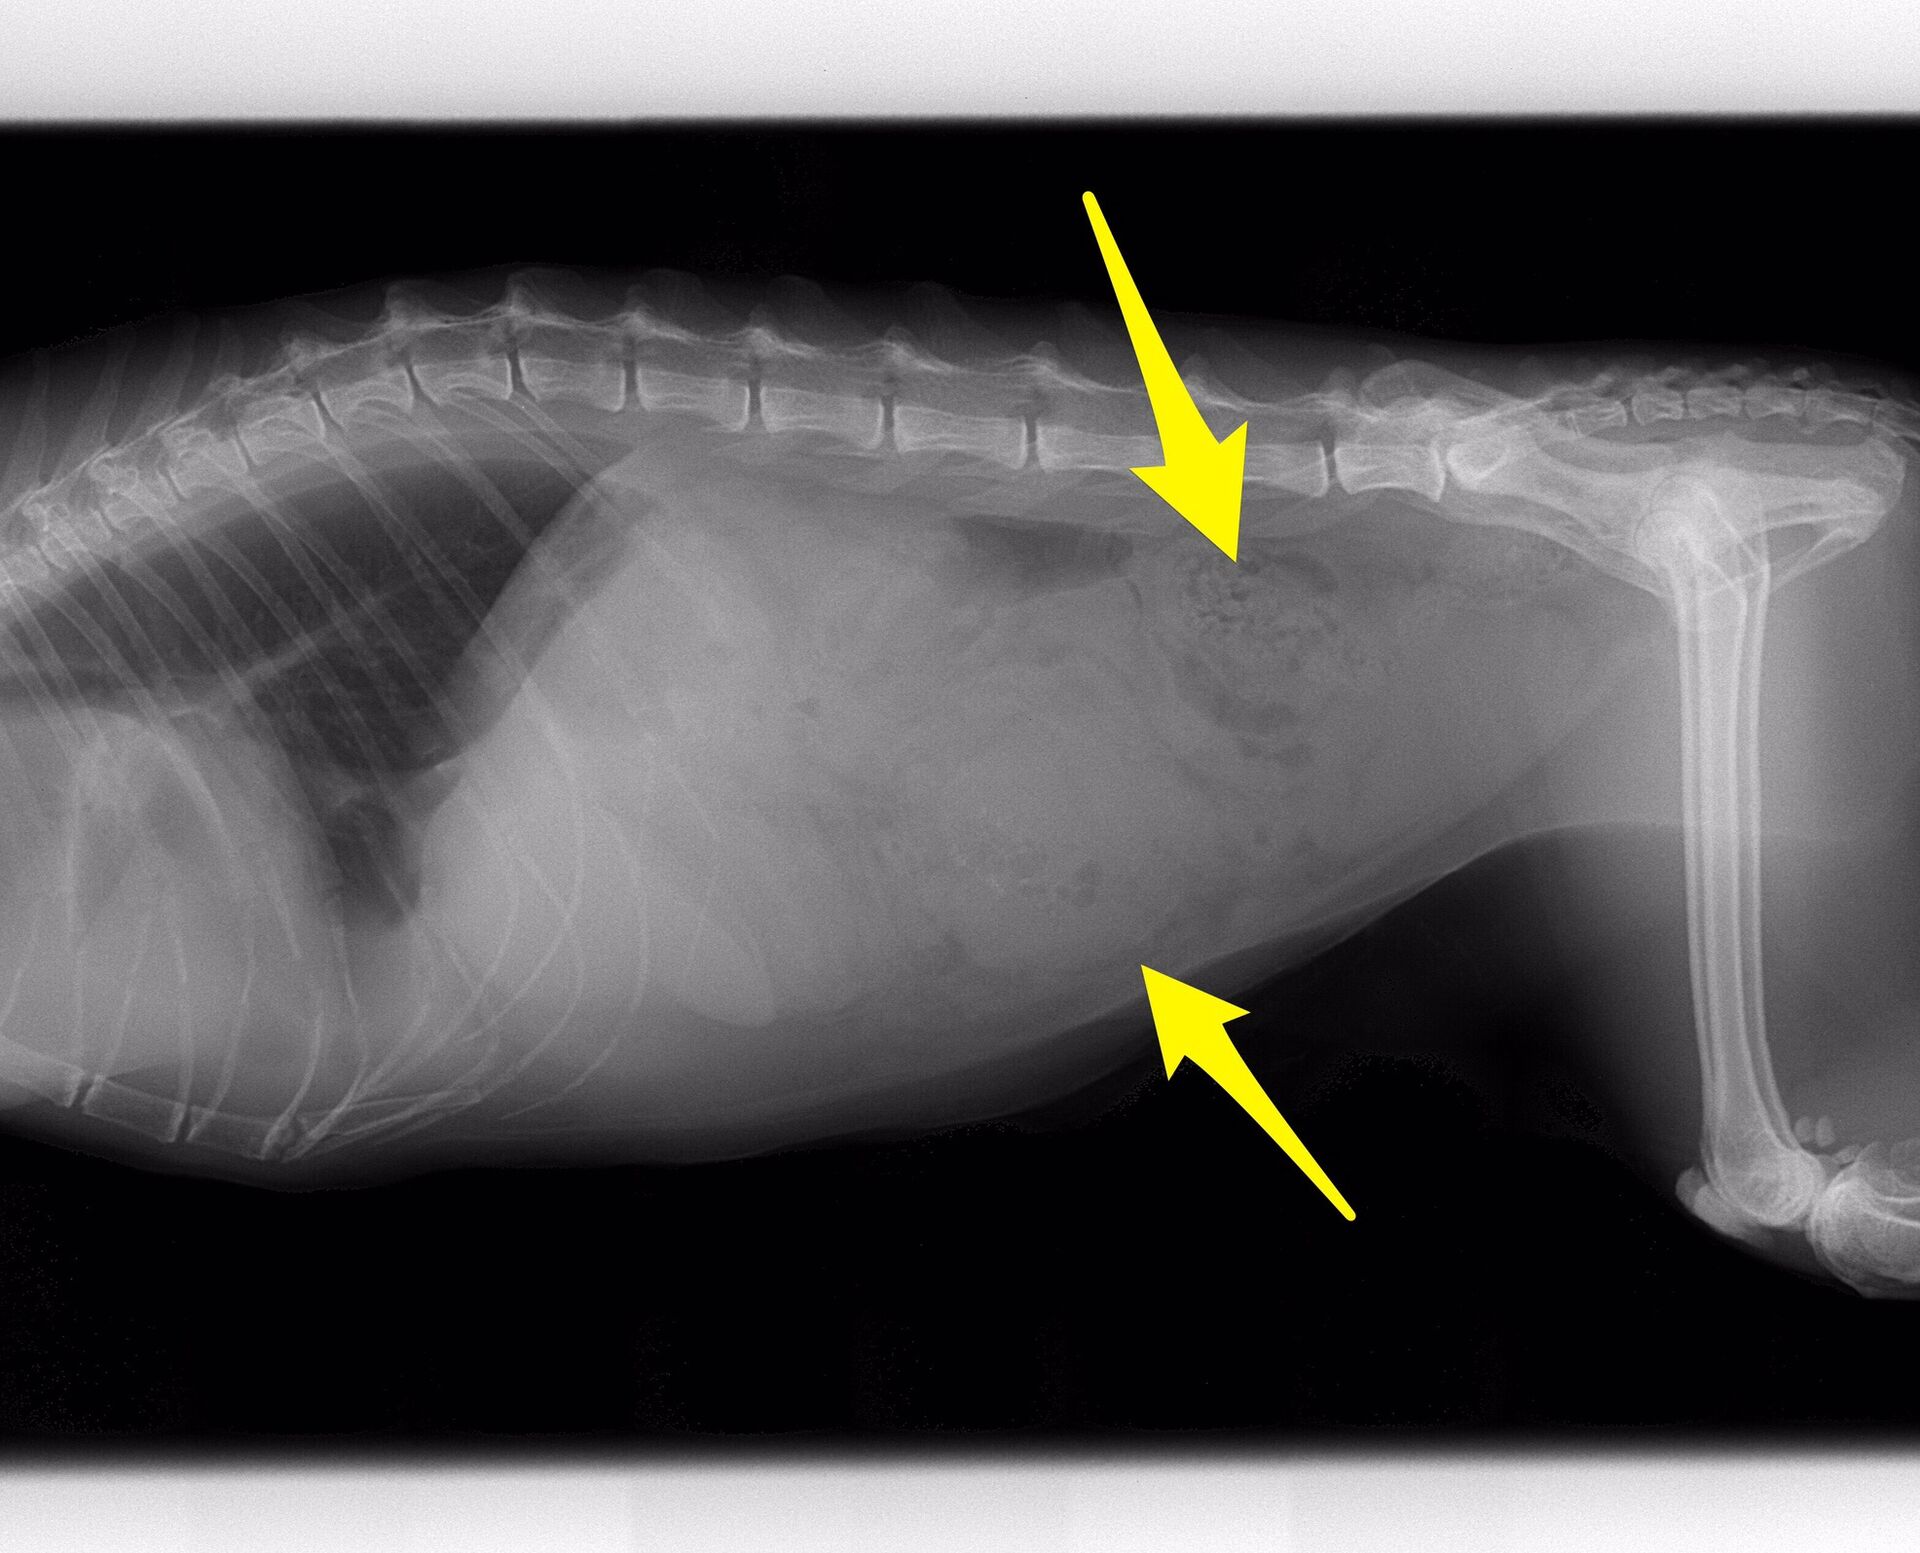

問題は腹部の腫瘤で、エコーとレントゲン写真を下に示します。

腹腔内に複数の腫瘤が認められましたので腸管膜のリンパ節が大きくなっていることが予想されました。飼い主さんと相談しまして、まずは開腹手術をして、切除できるものなら切除するということになりました。